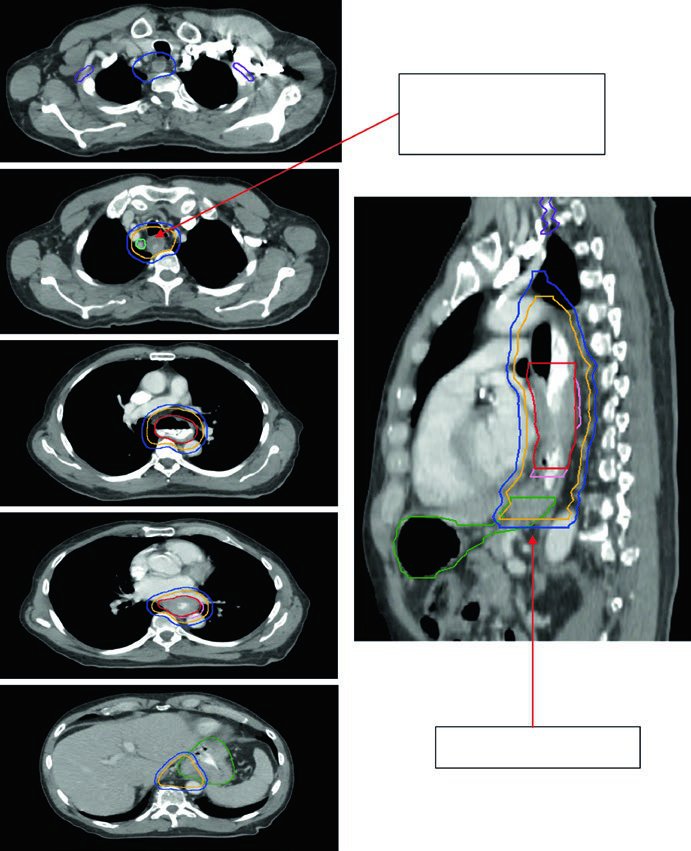

Case 1: Cervical/Upper Thoracic SCC — 69-Year-Old

A 69-year-old patient with SCC of the cervical/upper thoracic esophagus. PET-CT revealed FDG-avid primary and mildly avid paratracheal lymph nodes. EGD showed an ulcerating submucosal mass 15–23 cm from the incisors. Delineated volumes included: brachial plexus (purple), larynx (yellow), esophageal GTV (red), nodal GTV (green), CTV (orange), PTV 54 Gy (cyan), and PTV 60 Gy (dark blue). The superior border of the supraclavicular field was placed at the inferior border of the cricoid cartilage, with bilateral elective SCV nodal coverage.